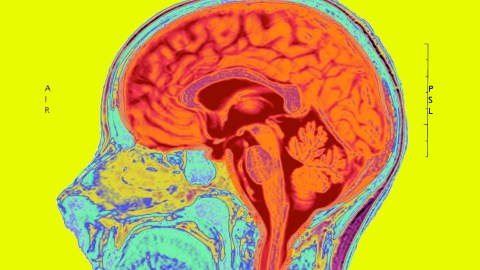

This misplaced reductionism arose from the availability of spectacular research tools (eg, the Human Genome Project, functional magnetic resonance imaging, molecular biology and machine learning) combined with the naive belief that brain biology could eventually explain all aspects of mental functioning. The results have been a grand intellectual adventure, but a colossal clinical flop. We have acquired a fantastic window into gene and brain functioning, but little to help clinical practice.

The more we learn about genetics and the brain, the more impossibly complicated both reveal themselves to be. We have picked no low-hanging fruit after three decades and $50 billion because there simply is no low-hanging fruit to pick. The human brain has around 86 billion neurons, each communicating with thousands of others via hundreds of chemical modulators, leading to trillions of potential connections. No wonder it reveals its secrets only very gradually and in piecemeal fashion.